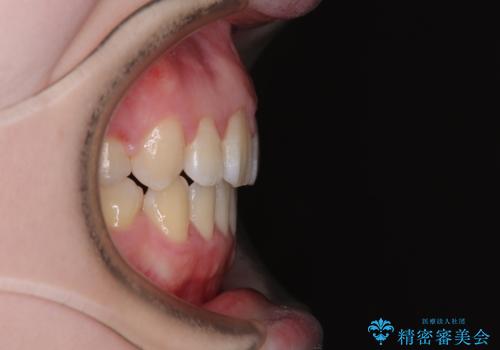

強い舌の突出癖により、上下前歯が前方に飛び出しており、特に上顎前歯は下顎よりも更に前方に位置している状態でした。

上顎前歯をしっかりと後方に移動させるため、口蓋側にアンカースクリューと補助装置を併用し、上下左右の第一小臼歯4本を抜歯し、ワイヤー装置にて矯正治療を行うこととしました。

口元の突出感が改善されてことで、下唇に引っかかっていた上顎前歯も気にならなくなりました。